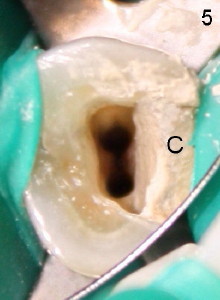

After removing DO caries and enlarging the access, it becomes obvious that there is a missing buccal canal (Fig.3 B). There is purulent discharge from the buccal canal in the beginning of the debridement. Fig.3 photo is taken after the buccal canal is fully shaped with rotary files (final file: 30/.06). Arrowhead points to the original lingual orifice with gutta percha. The RCT retreat is initiated on emergency basis. There is not enough time to remove the lingual gutta percha. More importantly, there is leakage of sodium hypochorite during irrigation due to large DO defect. After drying the buccal canal, the access is sealed with cotton pellet and Cavit. In fact the symptom and signs of reinfection disappear after initiation of RCT retreat. In the 2nd appointment, the occlusal portion of the Cavit is removed for accessing, leaving distal portion in place. The lingual gutta percha is removed and the lingual canal is re-shaped. Fig. 4 shows two master cones (30/.06). The buccal and lingual canals fuse at the apex. Fig.5 photo is taken after the two canals are dried. C stands for the remaining distal portion of the Cavit. There is no leakage during NaHOCl irrigation. Fig.6 shows the final obturation with with possible lateral canal filling (arrowhead). The access is again re-sealed with Cavit (C). Nine days later, the patient returns for prefabricated post and PFM preparation. Finally PFM is cemented. The patient remains asymptomatic.